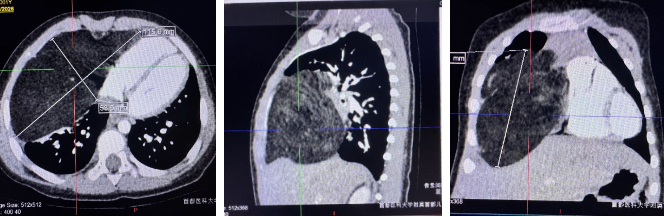

胸部增强CT提示前纵隔及右侧胸腔巨大占位,纵隔左偏,右肺受压